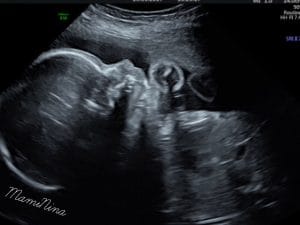

In resnično nam ni prav nič žal. Videli smo vse in to zelo dobro. Obrazek je seveda gospodična precej pokrivala, tako kot ga je tudi njena sestrica. In ne le to, prav tako kot sestrica, je tudi tale gospodična obrnjena v desno, pred obrazkom se nahaja tudi ena nogica in seveda kraljuje na svoji mali ritki.

Pogledali smo v njeno glavico, preverili srček, nogice, rokice, obrazek, mehur in na sploh vse. In vse izgleda prav super.

Seveda pa prilagam tudi 4D ultrazvok male zaspanke, ki je načeloma ves čas zelo aktivna, tokrat pa je na pregledu bolj ali manj počivala.